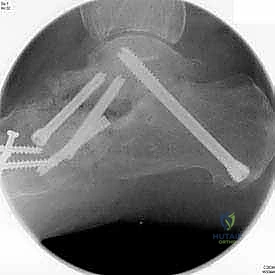

5. التثبيت الداخلي (Internal Fixation)

بعد التأكد من الوضعية المثالية للعظام، يتم تثبيتها بقوة باستخدام مسامير معدنية مجوفة من التيتانيوم (Cannulated Screws) أو شرائح معدنية خاصة. يتم إدخال المسامير تحت توجيه الأشعة السينية المباشرة (Fluoroscopy) داخل غرفة العمليات لضمان الدقة المتناهية. هذه المسامير تضغط العظام معاً وتمنع أي حركة حتى يحدث الالتئام التام.